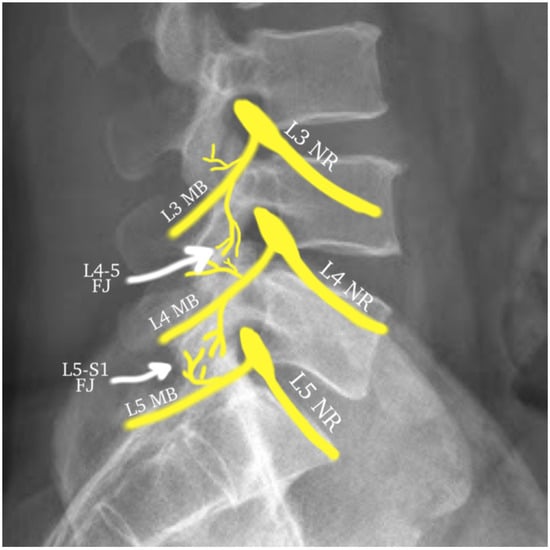

Figure 2.

The algorithm depicting a typical treatment protocol for facet joint pain with the goal of radiofrequency ablation after the likelihood of diagnosis increased by two dual diagnostic blocks.